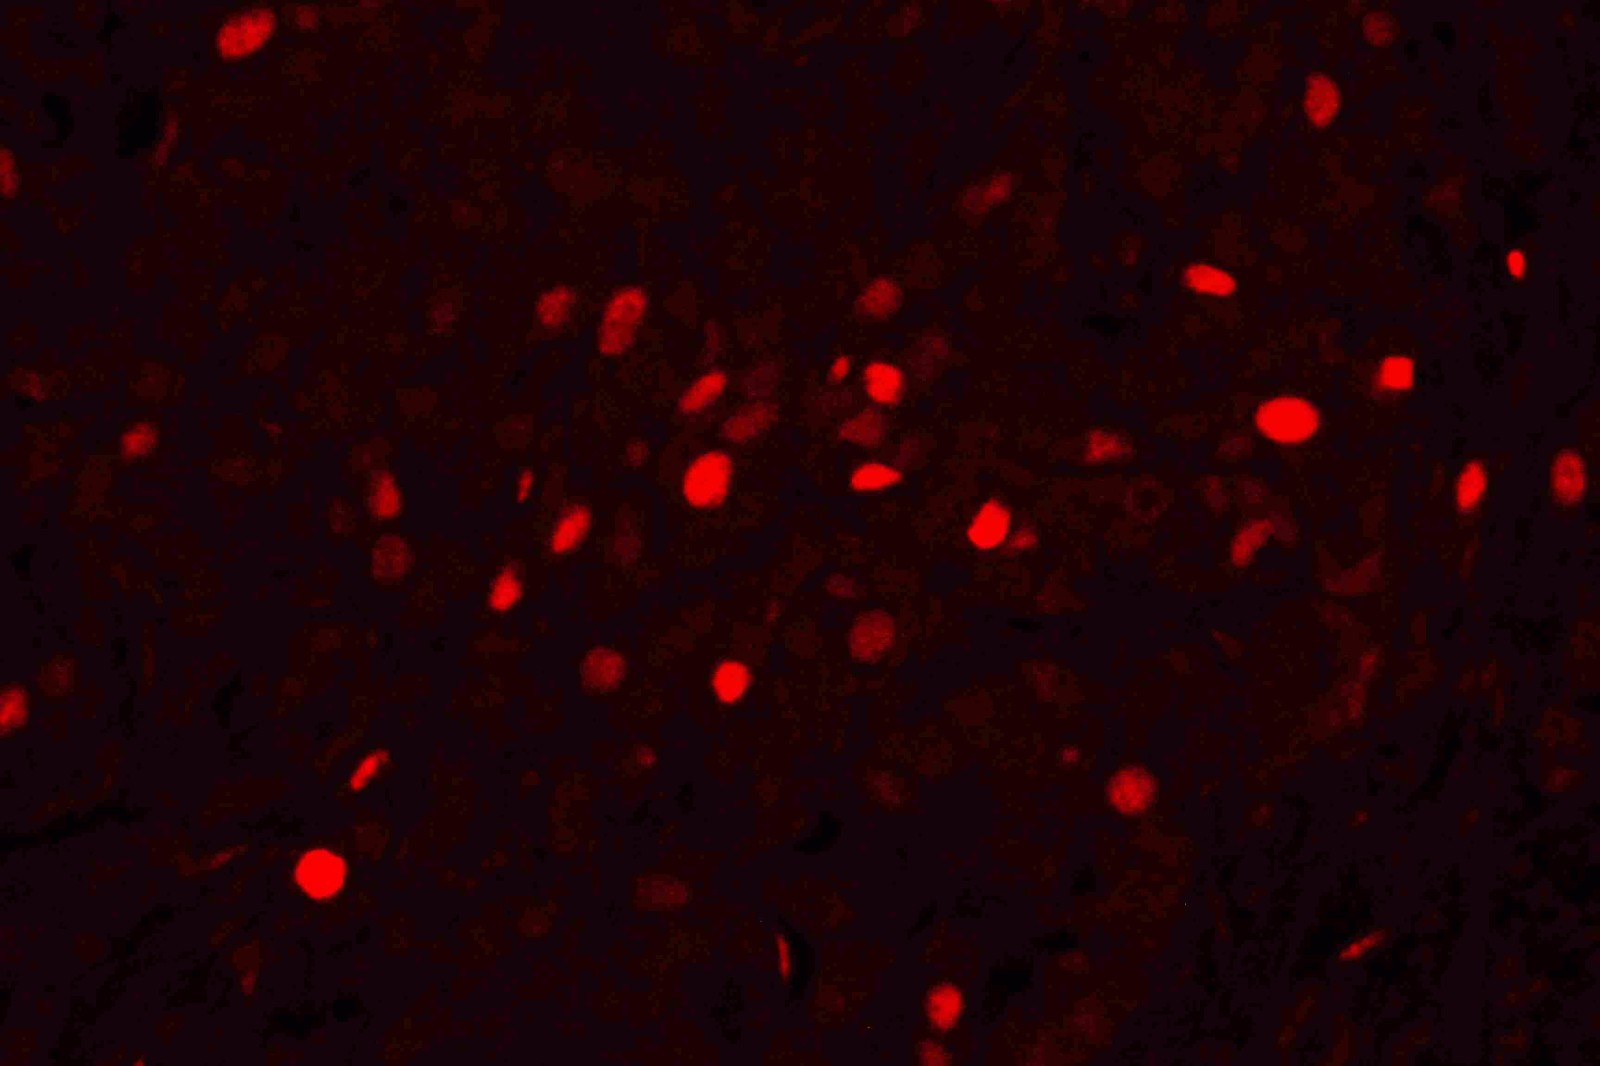

IF analysis using Anti-PCNA antibody(BM0104) detected in paraffin-embedded section of human lung cancer tissue. The tissue section were stained using the TRITC Conjugated AffiniPure Goat Anti-mouse IgG (H+L) Secondary Antibody (red)(Catalog#BA1089) and counterstained with DAPI (blue).